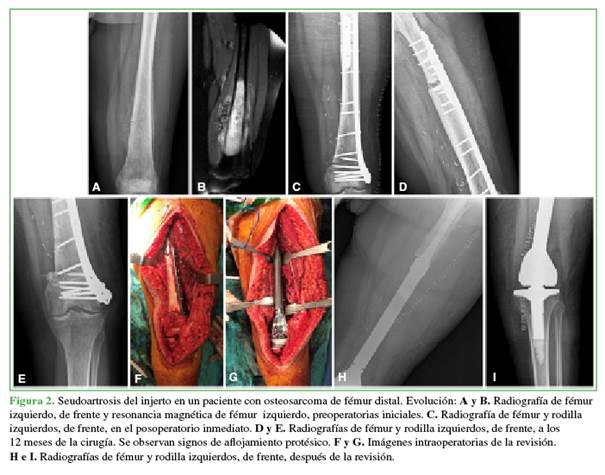

Se analizaron 12 prótesis en 11 pacientes (9 primarias y 3 revisiones). Seis pacientes eran hombres y cinco, mujeres. La edad promedio era de 60 años (rango 16-87). El seguimiento varió de 6.2 años a 11 meses (promedio 3.8 años). En la Tabla 1, se detallan los diagnósticos. En total, se habían colocado nueve prótesis por enfermedades no neoplásicas y tres por cuadros posneoplásicos (un aflojamiento aséptico, una seudoartrosis del injerto óseo y una rotura del implante) (Figuras 1-3).

El implante falló en dos pacientes (18%) y las causas fueron: una infección y un aflojamiento aséptico. El primer caso (paciente 5) fue una paciente que sufrió una infección del sitio quirúrgico luego de una artroplastia total de rodilla primaria, y requirió una reconstrucción con endoprótesis de rodilla luego de tratar la infección. Finalmente, a causa de otra infección, se retiró la endoprótesis y se colocó un espaciador con antibiótico. Luego de esto, se perdió el seguimiento de la paciente. El segundo (caso 9) fue un paciente que sufrió una fractura de fémur distal que evolucionó a seudoartrosis y se le colocó una endoprótesis de rodilla. A los 40 meses, debió ser sometido a una cirugía de revisión por aflojamiento aséptico de la prótesis.